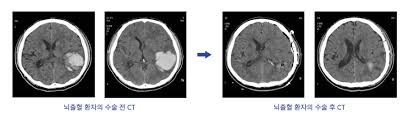

뇌출혈 수술은 뇌혈관이 파열돼 뇌 안에 피가 고인 상태를 제거하거나 압박을 완화하는 수술로, 이후 **의식회복 여부는 환자 예후를 결정하는 핵심 요소**입니다. 회복은 개인의 상태, 출혈 부위와 범위, 나이, 기저질환 등에 따라 크게 차이가 있으며, 적절한 치료와 재활, 가족의 지지가 매우 중요합니다.